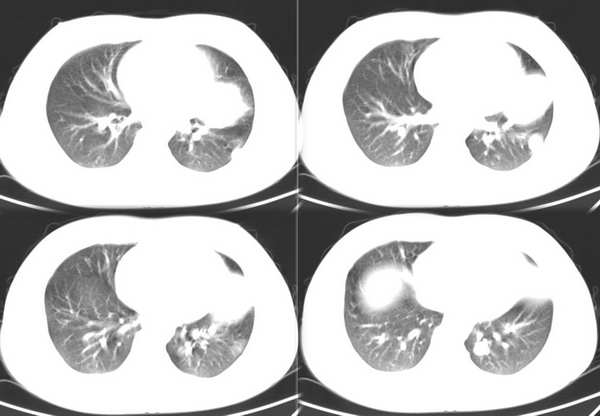

男,18岁。咳嗽,胸闷4天。

肺转移